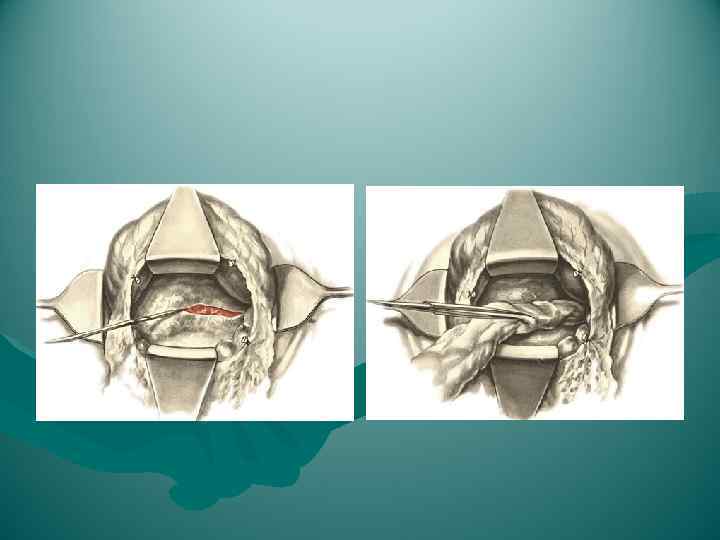

1) между желудком и поперечной ободочной кишкой, через желудочно-ободочную связку; этот способ самый удобный и его применяют чаще всего для обнажения всей передней поверхности поджелудочной железы; 2) через малый сальник; такой подход менее удобен и применяется редко, главным образом при опущении желудка; 3) через брыжейку поперечной ободочной кишки слева от позвоночника; этот доступ иногда применяют при кистах поджелудочной железы.

1) между желудком и поперечной ободочной кишкой, через желудочно-ободочную связку; этот способ самый удобный и его применяют чаще всего для обнажения всей передней поверхности поджелудочной железы; 2) через малый сальник; такой подход менее удобен и применяется редко, главным образом при опущении желудка; 3) через брыжейку поперечной ободочной кишки слева от позвоночника; этот доступ иногда применяют при кистах поджелудочной железы.